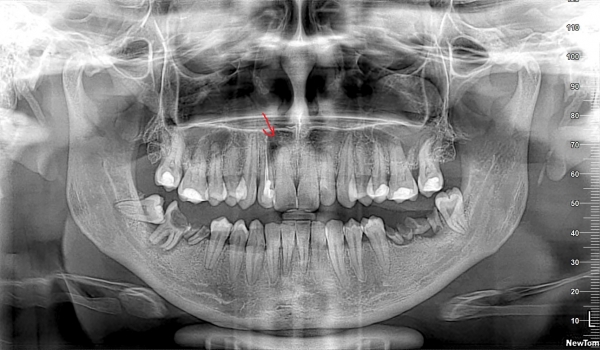

Мне лечили зуб, удалили нерв и запломбировали. Через 5 дней после лечения опухло лицо, и поднялась температура. В больнице сделали разрез десны и поставили дренаж. Сейчас принимаю антибиотики. Снимок сделан сразу после постановки дренажа. Сейчас, ничего не болит и опухоль спала.

На верхнем переднем зубе справа, это киста?

Да, это киста. Также огромная проблема на нижней челюсти, которая требует немедленного вмешательства.